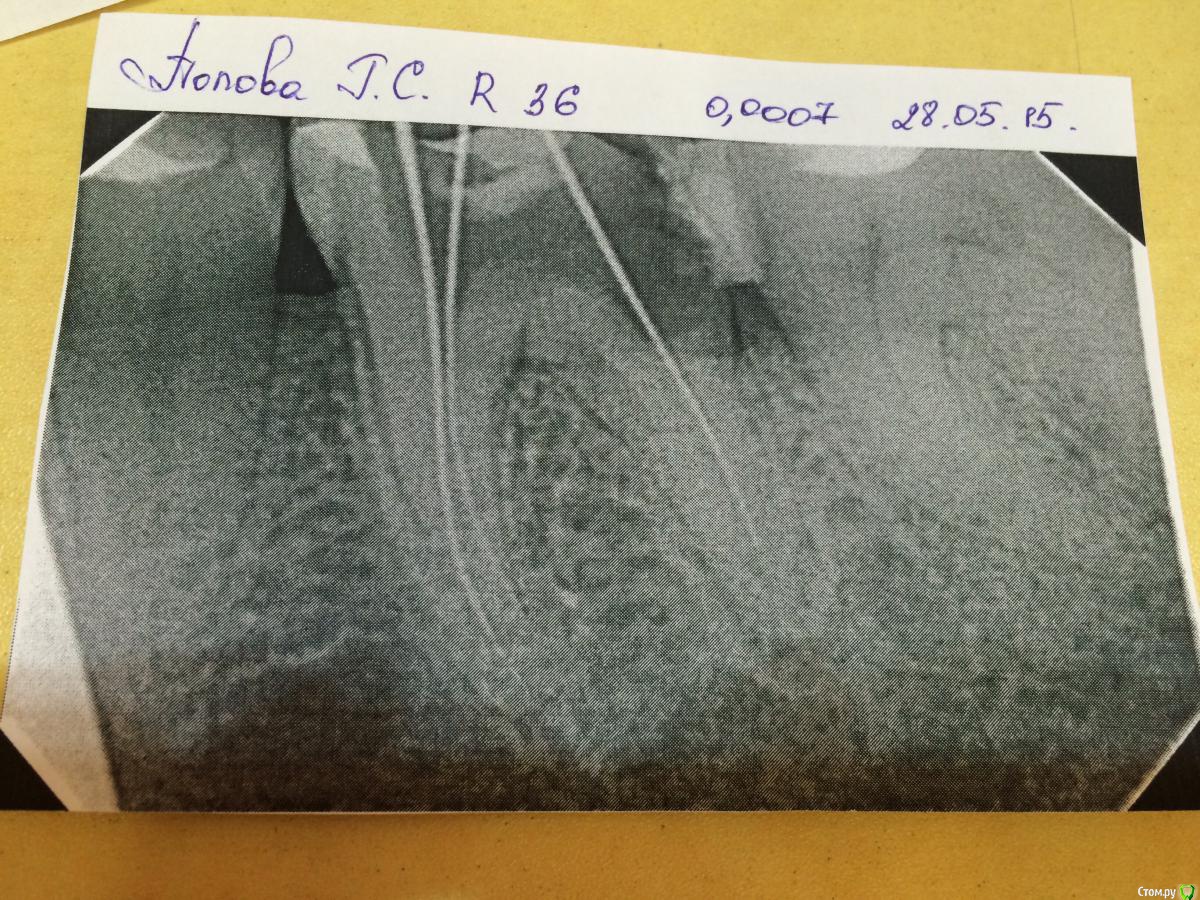

Belladonna.feo Опубликовано 28 мая, 2015 Поделиться Опубликовано 28 мая, 2015 (изменено) 36 зуб. Диагноз: хр.пульпит. Медиальные каналы пройдены до апекса(исходя из данных Р-снимка и апекс локатора), дистальный на 2/3 и далее нет прохода. Апекс локатор показывает выход за апекс, на снимке будто в канале. Пациент под анестезией, поэтому боли нет. Кровотечения из канала тоже. Что посоветуете делать? An. Morbi: пациентка пришла с жалобами на ноющие боли в левой челюсти. Указывала на 37 зуб. После просмотра снимка пришли к решению, что причина болей пульпит в 36 з, по причине глубокой кариозный полости. На 37 разрежение в обл дист корня и кариоз полость под пломбой. Ретинированный 38. В 36 на устьях был оставлен нон арсеник на 8 дней. Далее вновь анестезия и депульпация. Медиальные обработаны протепейрами 06 до 20 номера. Дистальный не пускает и не кровоточит. Показывает апекс. Изменено 28 мая, 2015 пользователем Belladonna.feo Ссылка на комментарий

Ker Опубликовано 10 марта, 2016 Поделиться Опубликовано 10 марта, 2016 (изменено) кстати вглядитесь во второй снимок, там видно докуда канал идет. Нет никакого перфо там. А инструмент не идет из опилок. Имхо. Изменено 10 марта, 2016 пользователем Ker Ссылка на комментарий